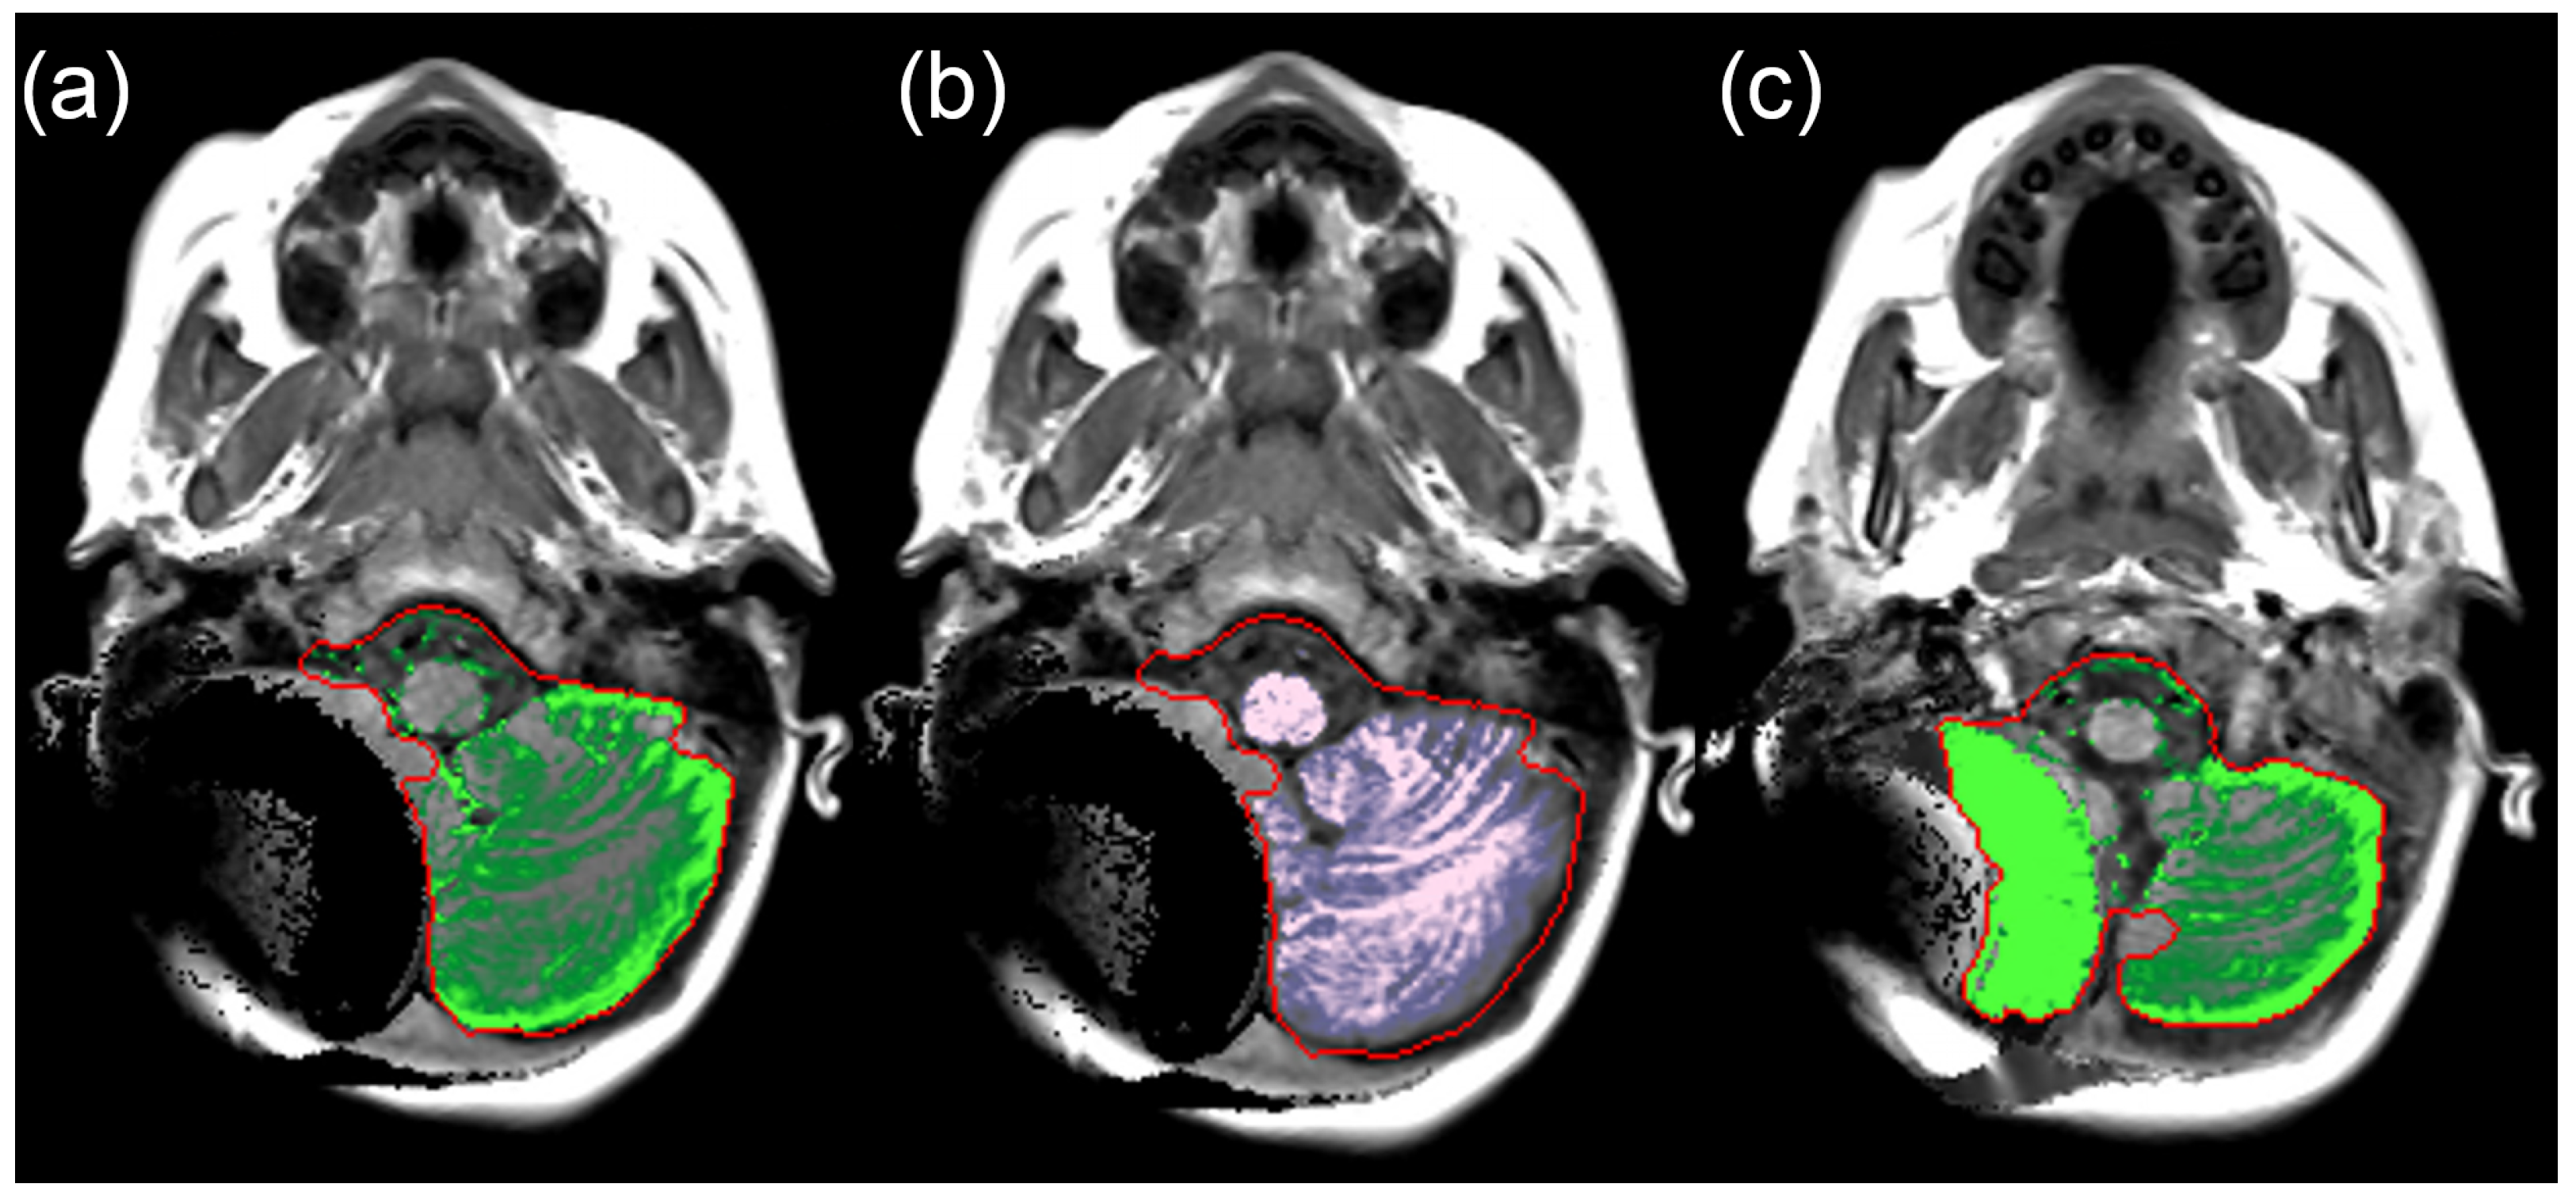

2.2. SyMRI Volume Measurements

2.3. Manual Volume Measurements